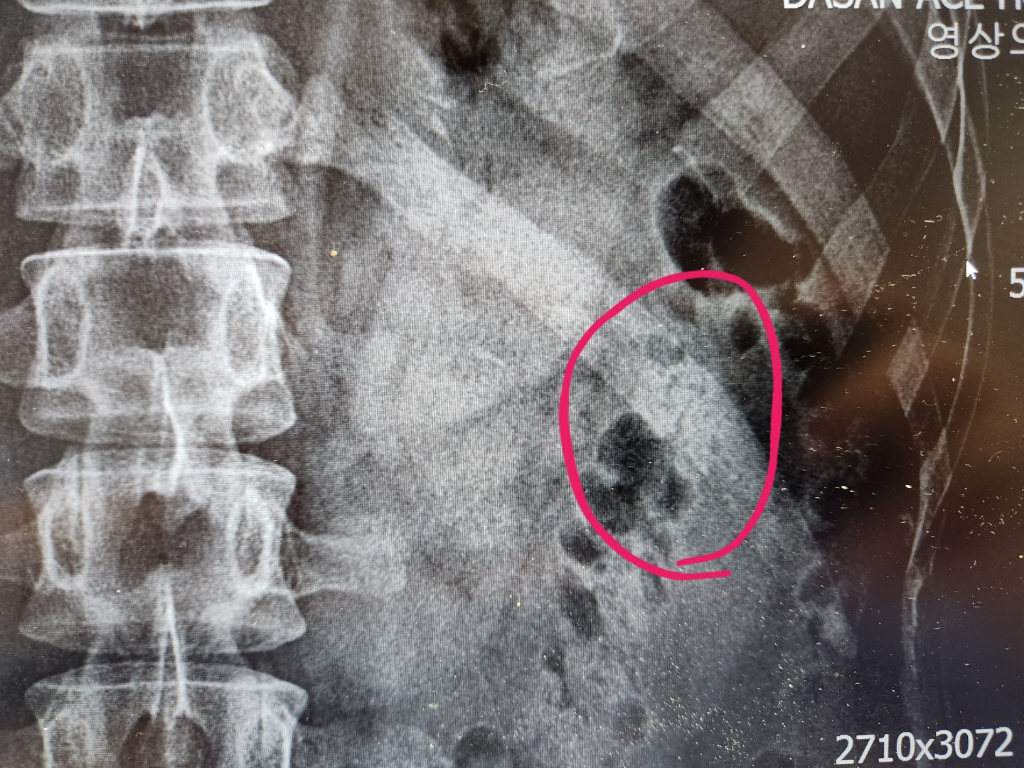

- 흉부 X-ray: 기본적으로 갈비뼈 골절 여부 확인 시 가장 많이 활용됩니다.

- CT(컴퓨터 단층 촬영): X-ray에서 확인이 어려운 미세골절, 연골 손상, 내부 출혈까지 파악 가능.